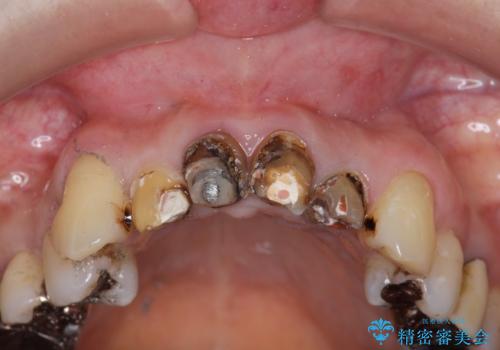

以前に治療した前歯クラウンは月日が経過することで劣化・歯肉の位置変化を引き起こし審美障害を引き起こしています。

劣化したクラウンを除去し、再発した虫歯を徹底的に除去したのち根管治療・ファイバーコア築盛を行いジルコニアクラウン製作へと移ります。